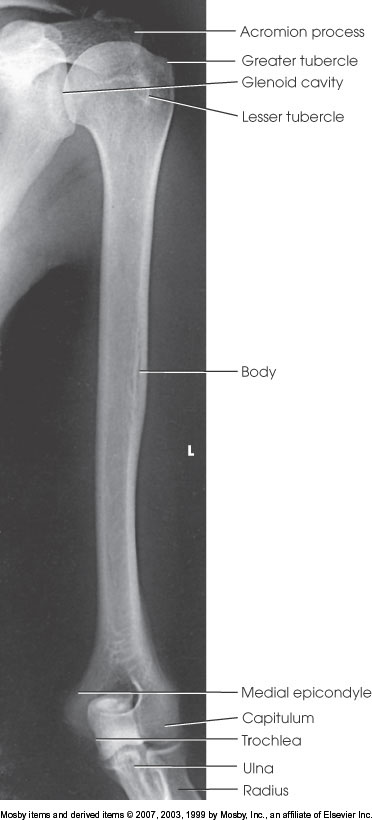

AP Humerus

What position is demonstrated?